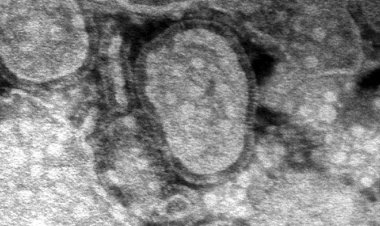

По её словам, картофель обладает противовоспалительным эффектом и позволяет укрепить мелкие капилляры и сосуды. На это влияет такое соединение, как кверцетин. Диетолог подчеркнула, что именно кверцетин был востребован в период пандемии коронавируса: вещество улучшает работу дыхательной системы, бронхов и лёгких.